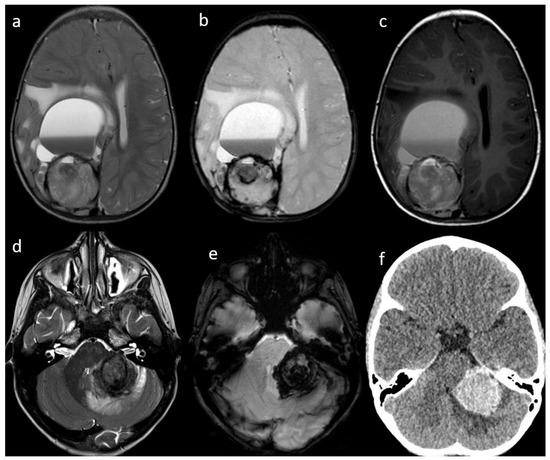

| 1 | brain parenchyma | right cerebral hemisphere | 1 | 90 × 60 × 50 | CT MRI | yes | Yes | yes | yes | yes | N/A | N/A | performed after surgery |

| 5 | brain parenchyma | left cerebellar hemisphere/middle cerebellar peduncle | 1 | 30 × 30 × 36 | CT MRI | yes | High | no | yes | yes | N/A | N/A | negative |